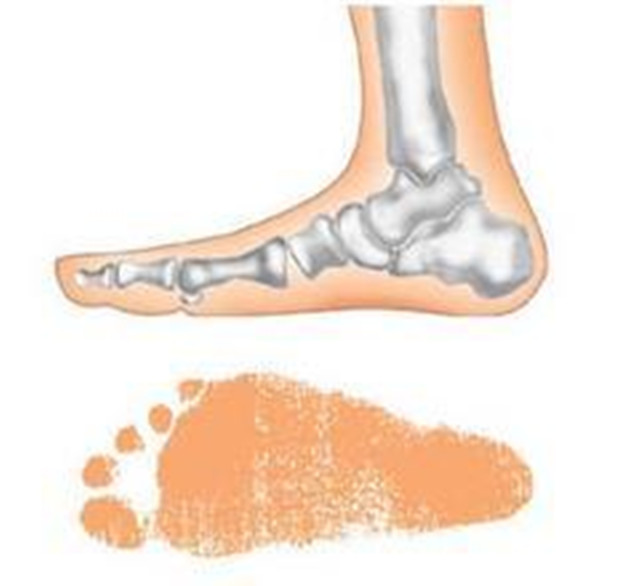

一、 先来了解下什么是“扁平足”

如何判断自己是不是扁平足呢?其实很简单,把鞋子脱了以后光脚站在地上,如果整个脚底都贴在地面上,那你就是典型的扁平足了。再一个就是从侧面观察自己的脚底,正常人的脚是有明显的弯曲的足弓的,而扁平足则是一条直线。